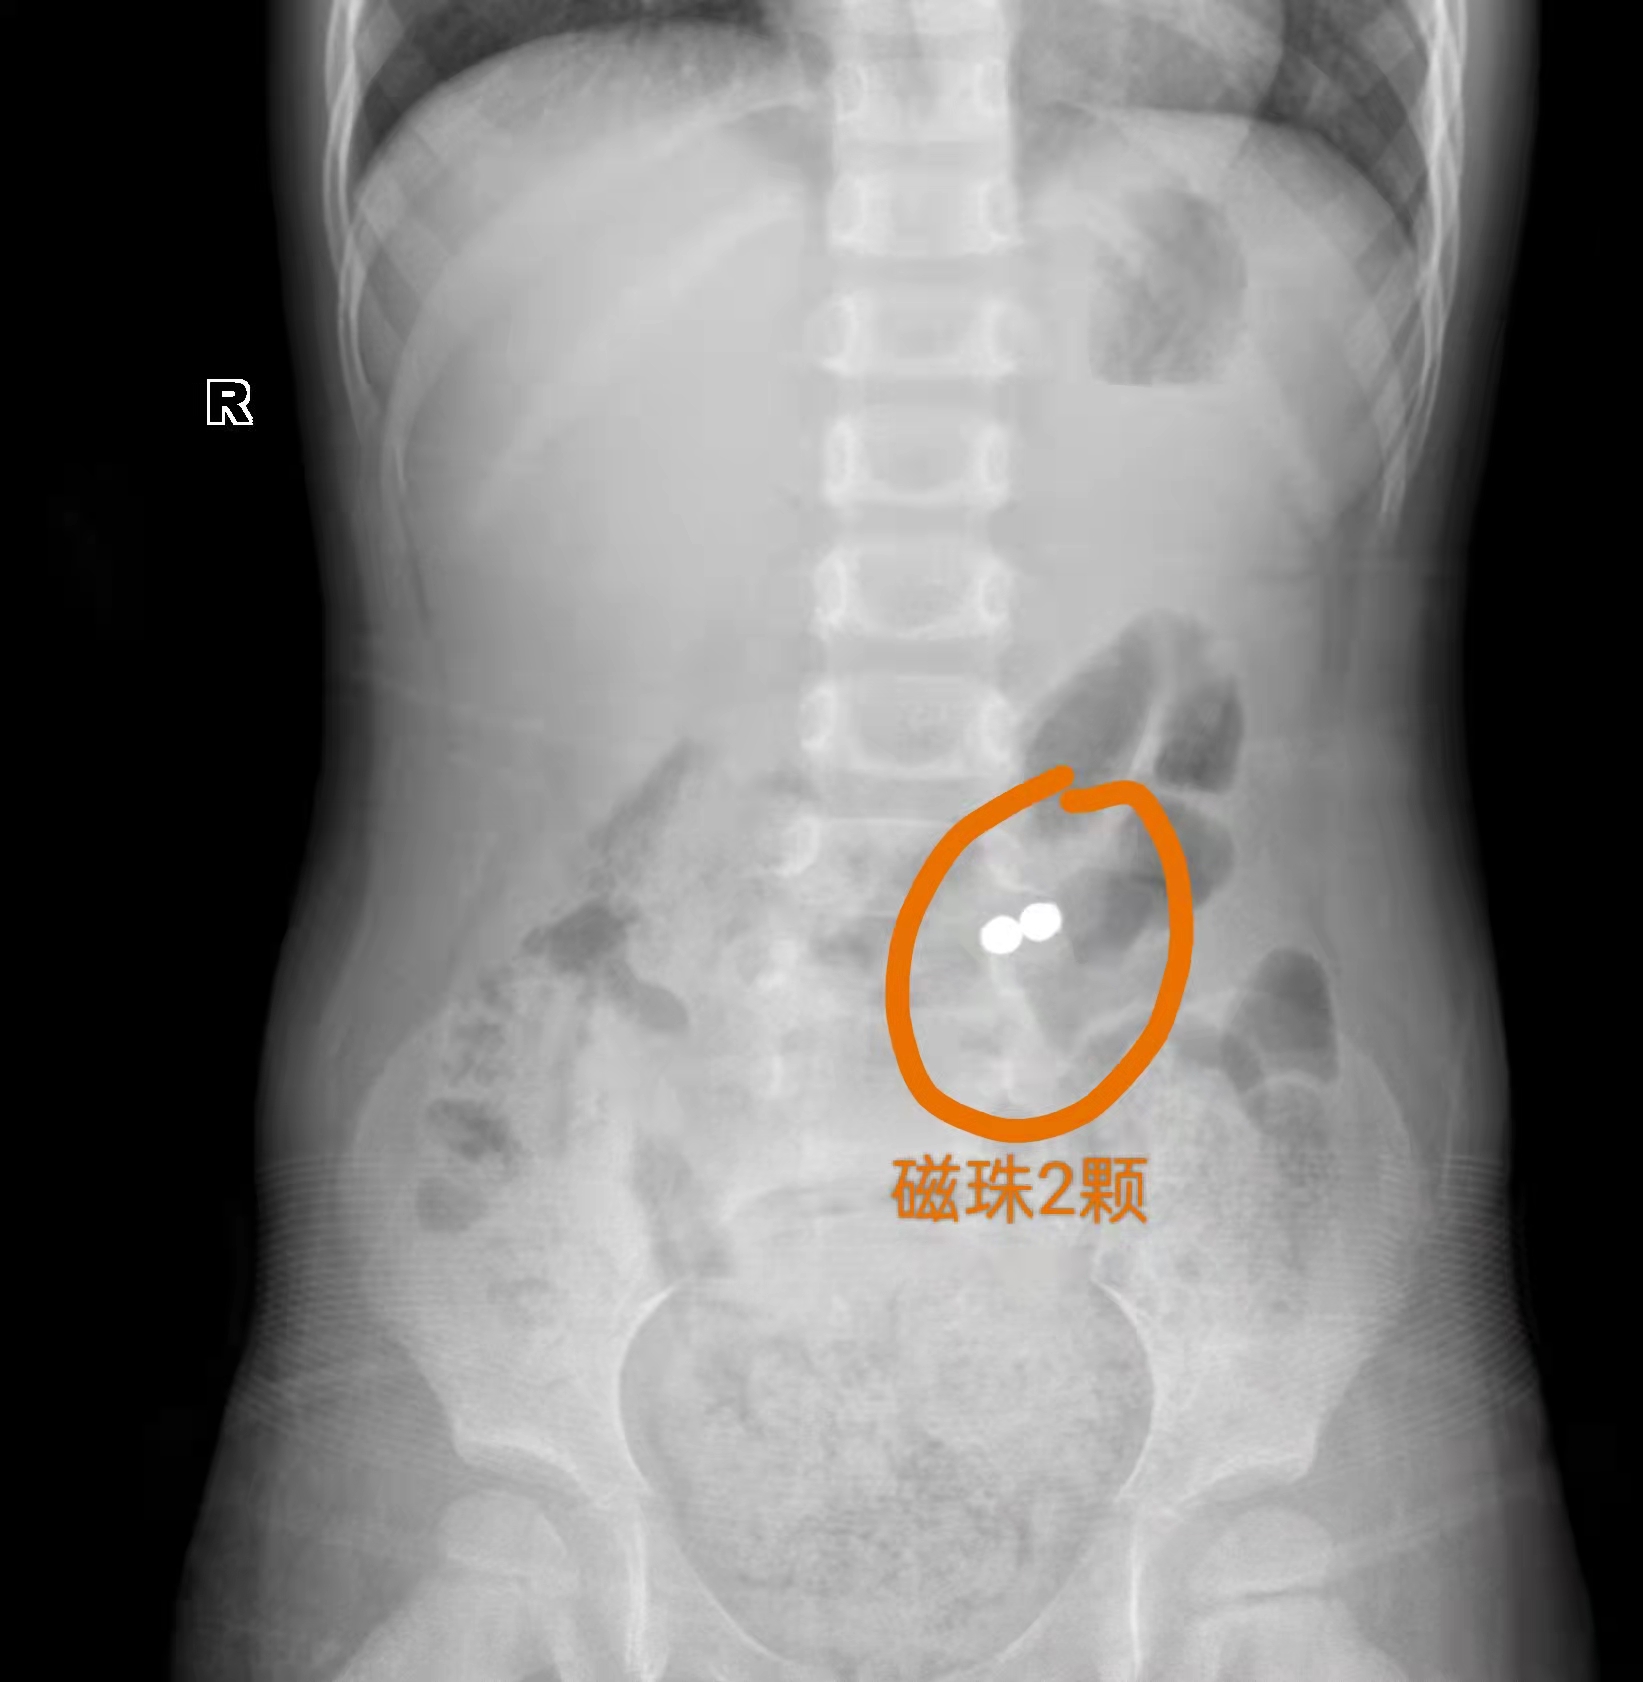

3岁6个月的玲玲1月前因咳嗽就诊于当地医院,医生考虑肺炎,予做胸片检查,结果发现腹部消化道异物,当时玲玲并无腹痛、呕吐等,医生建议暂时先观察,看能否自行排出,如有不适随诊。虽然1个月来一直没有腹痛、呕吐等症状,但异物却迟迟没有排出,家长心理十分担心,便就诊于湖南省儿童医院普外二科。4月12日,医生为其行了腹腔镜下消化道异物(磁珠)取出,肠修补手术。

起初妈妈看到X片的结果肯定的说孩子腹部的异物为纽扣电池,因其妈妈在自已家中做电池手表安装的工作,据妈妈回忆她隐约记得一个月前丢失过2粒纽扣电池,因丢失2粒纽扣电池并不会影响她的正常工作,所以未仔细寻找。但经医生术后取出异物是2颗磁珠,妈妈不断问自己,我家从没见到过这种磁珠?磁珠从何而来呢?玲玲又是何时误吞磁珠的呢?妈妈打电话询问家里人,家里人都说在家里未见过这类磁珠。

这种磁珠就是市面上出售的巴克球,巴克球为一款国外流行并进入国内的成人解压磁性球,绝非宣传的“益智玩具”。前几年德国和美国都曾召回过磁珠类玩具,原因都是因为这些磁珠的外观对幼儿特别具有吸引力,因其尺寸和形状容易被孩子放进嘴里,导致严重后果。市面上的磁珠玩具色彩漂亮,吸力又极强,2颗磁珠即使相距10厘米仍可吸在一起。它借助金属球的磁场特性,可以组合出众多的造型。巴克球因颜色鲜艳,直径5毫米左右,让不少小孩将其误当成糖果。误食巴克球会引起胃肠穿孔或是肠梗阻。磁珠误吞一颗其实并不可怕,就怕多个磁球一块误吞。多颗磁珠会因为吸力的相互吸引,造成胃肠道穿孔或梗阻的现象,一旦耽误病情,造成腹腔的重症感染,会危及生命。

玲玲比较幸运的是肠穿孔后形成了肠内瘘,并未造成腹腔的重症感染、腹膜炎等情况,可以说是不幸中的万幸,湖南省儿童医院普外二科手术团队通过微创手术解决了玲玲的大问题,腹部最大伤口手术约1cm。每年,湖南省儿童医院普外二科收治需要手术取出的误吞磁珠病例就有二十余例,特别提醒家长们,不要太小看孩子的好奇心,不要给孩子买磁珠类玩具。